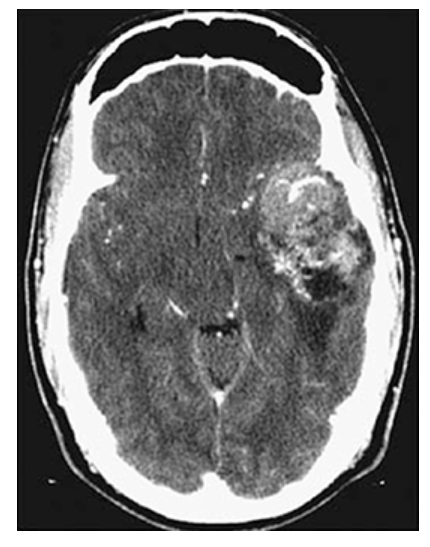

Astrocytoma. Axial CECT shows mild enhancement of the mass which contains areas of necrosis.